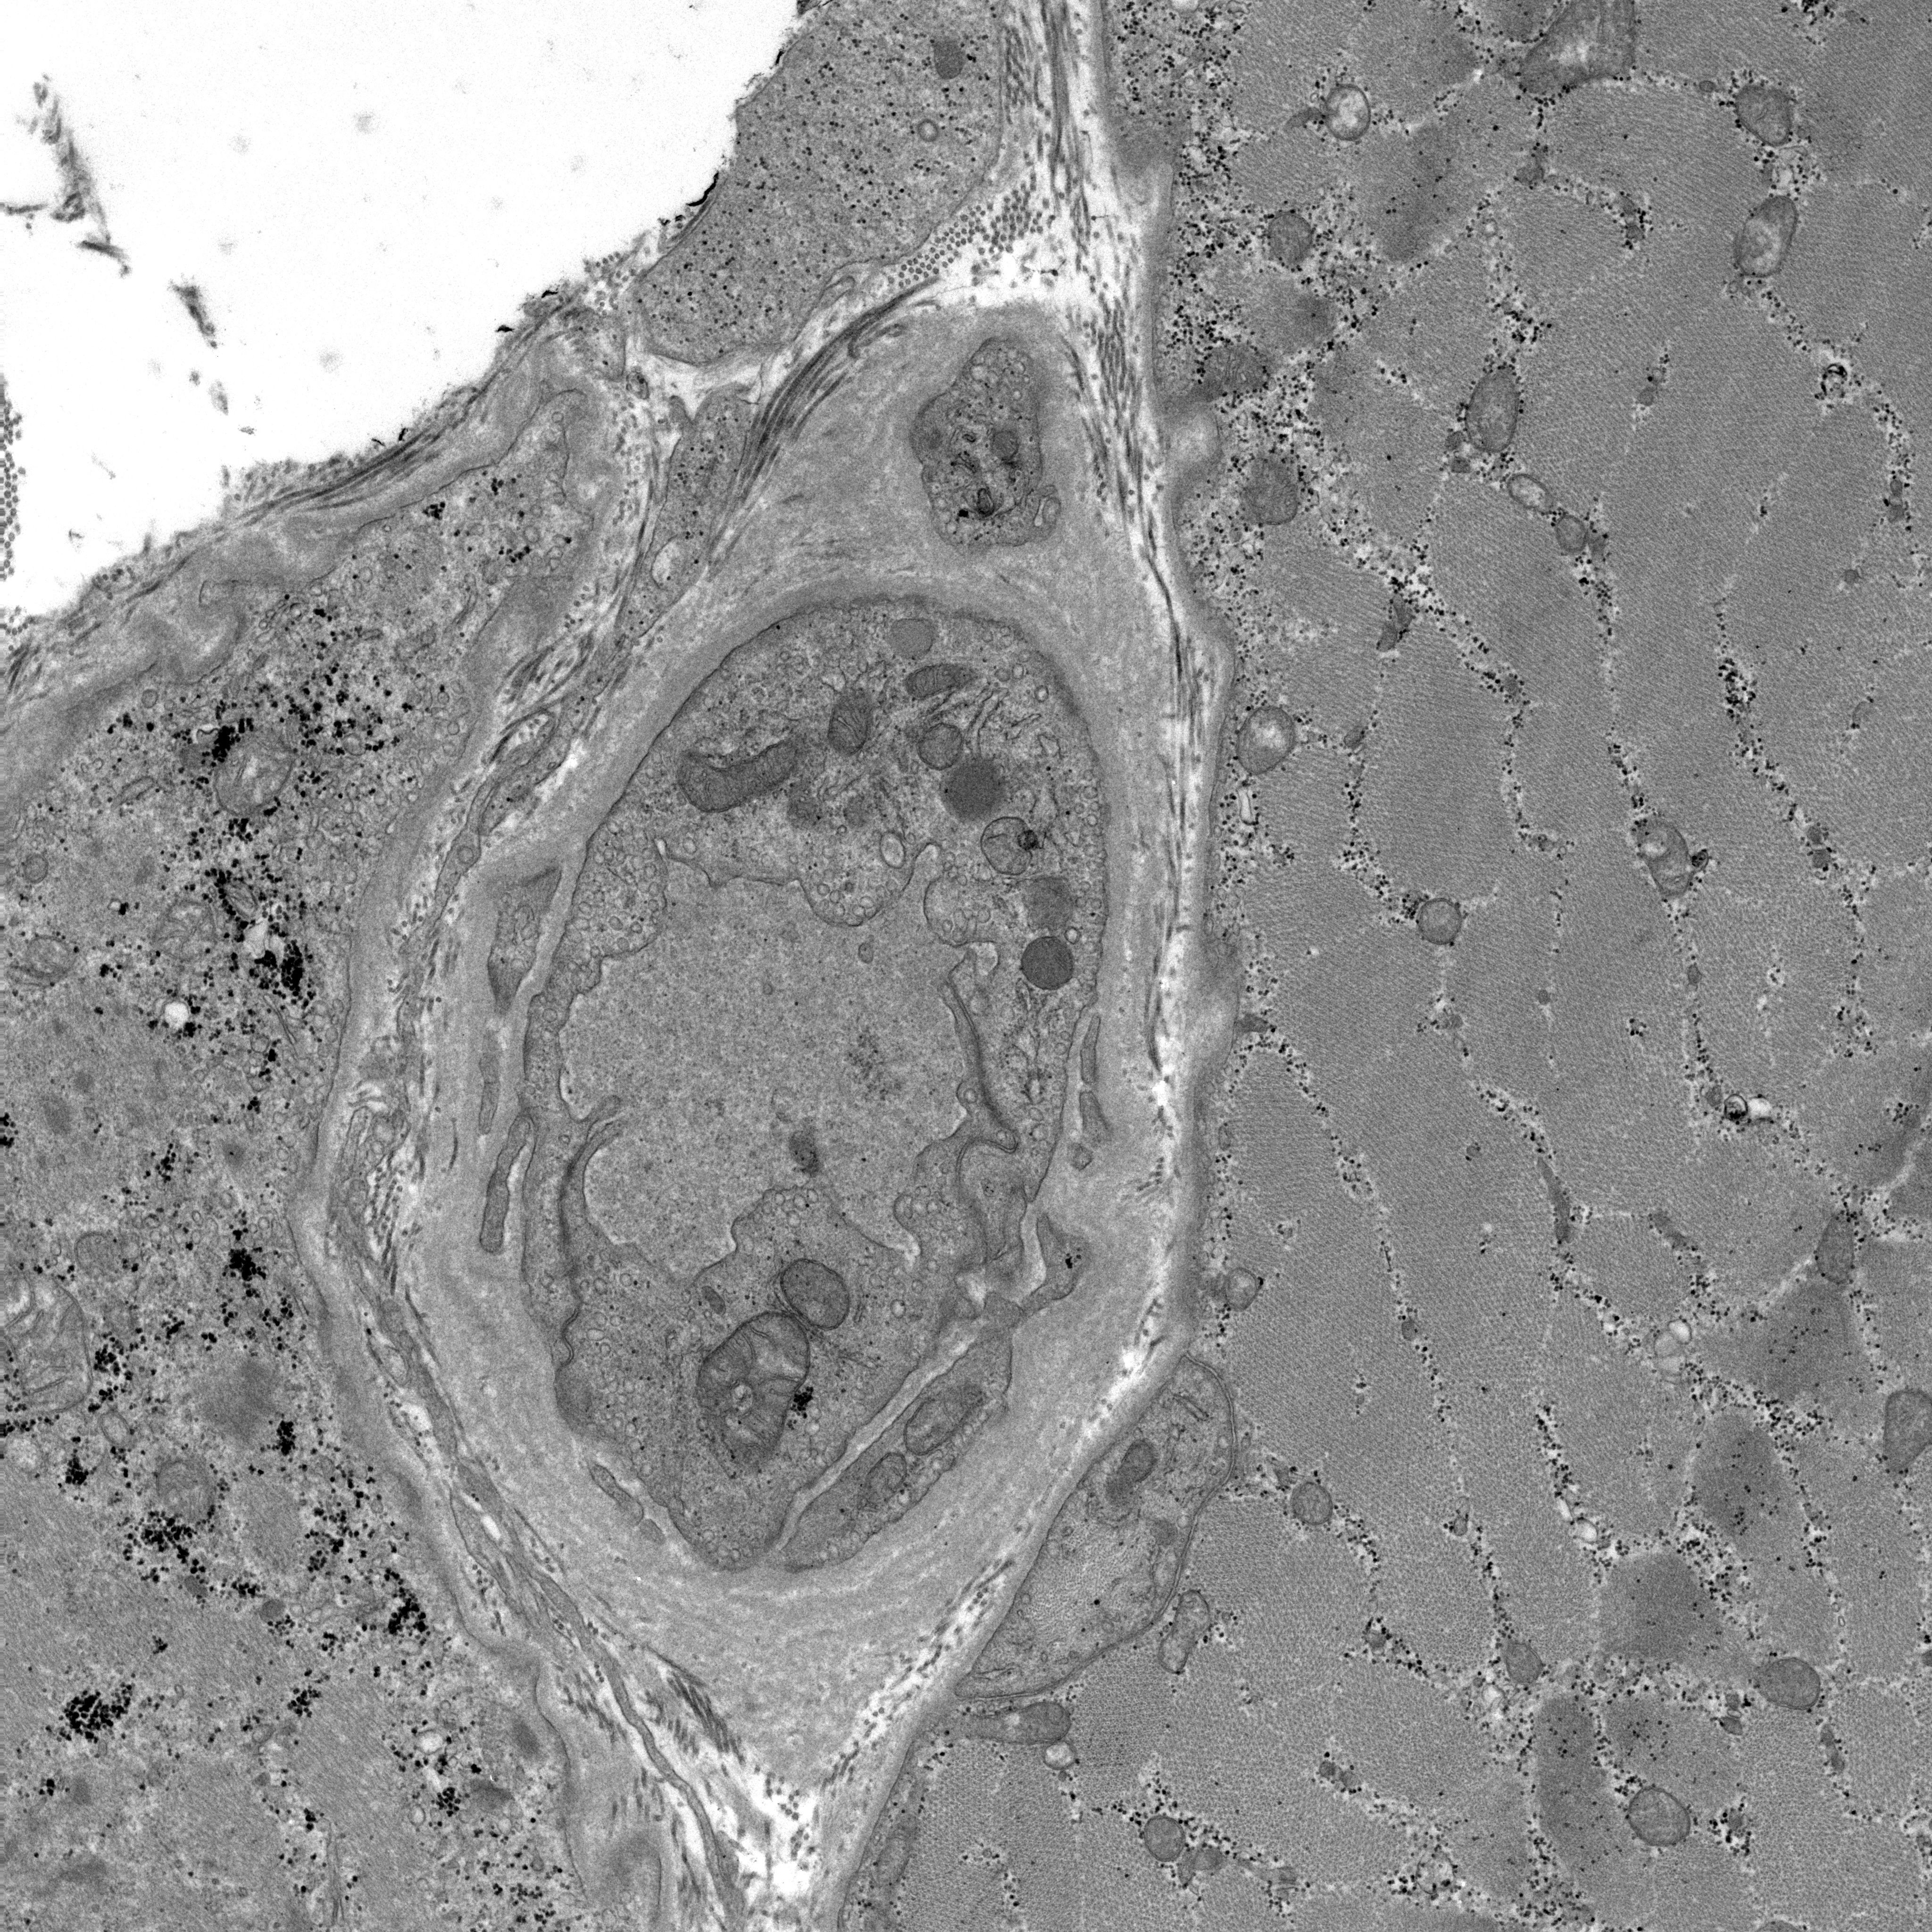

Case 13_EM.jpg